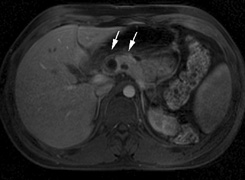

CNS hemangiomas are the most common tumor of VHL, affecting 60% to 80%, with a predilection for the cerebellum and spinal chord. An enlarging cystic component is a frequent finding in symptomatic tumors. Patients typically present in their early 30s; headaches or neck pain in affected individuals should not be ignored.172,173 On microscopy, CNS hemangiomas resemble retinal capillary hemangiomas. Their malignant potential is low.174 The treatment is surgical (Fig. 17, A and B).13

Fig. 17. Images from a 13-year-old boy with Von Hippel-Lindau syndrome. (a) Coronal postcontrast T1-weighted imaging reveals a cystic lesion with an enhancing nodule at the pial surface typical of a hemangioblastoma. (b) A second solid enhancing hemangioblastoma is seen at the craniocervial junction on a sagittal postcontrast T1-weighted image. (c) Associated cystic lesions (arrows) are seen within the pancreas.

Pancreatic lesions may be nonsecretory (most commonly cysts or cystadenomas) or secretory (islet cell tumor).179 In one study of 52 patients, 56% (29 patients) were found to have pancreatic lesions. The majority (19 of 29) had cystic changes only (Fig. 17C). Pancreatic lesions were the only abdominal manifestation of disease in 6 of 52 patients.180 In a separate study, pancreatic cysts did not show significant progression on follow-up examinations over an average period of 5 years.181 Like pancreatic cysts, islet cell tumors appear to be frequently asymptomatic.182